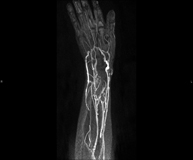

Prova diagnòstica no invasiva que consisteix en l'estudi de l'artèria aorta abdominal per obtenir imatges d'alta definició anatòmica mitjançant l'ús d'un camp electromagnètic i ones de ràdio (amb un emissor i un receptor). És indispensable l'ús de contrast intravenós paramagnètic (Gadolini). No obstant, no utilitza radiació ionitzant. La qualitat de les imatges permet realitzar reconstruccions en 2D i 3D. Està especialment indicada en pacients amb sospita de malaltia vascular de les dues extremitats, en pacients amb malaltia vascular de les dues extremitats com a mapa vascular abans del tractament (percutani o quirúrgic), com a mapa vascular prequirúrgic en pacients amb lesions òssies o musculars que requereixin cirurgia, etc. - Angio-RM Lesió de parts toves

Prova diagnòstica no invasiva que consisteix en l'estudi de les artèries de la cintura escapular, el braç, l'avantbraç i la mà per obtenir imatges d'alta definició anatòmica mitjançant l'ús d'un camp electromagnètic i ones de ràdio (amb un emissor i un receptor). És indispensable l'ús de contrast intravenós paramagnètic (Gadolini). No obstant, no utilitza radiació ionitzant. La qualitat de les imatges permet realitzar reconstruccions en 2D i 3D. Està especialment indicada en pacients amb sospita de malaltia vascular de les dues extremitats, en pacients amb malaltia vascular de les dues extremitats com a mapa vascular abans del tractament (percutani o quirúrgic), com a mapa vascular prequirúrgic en pacients amb lesions òssies o musculars que requereixin cirurgia, etc.